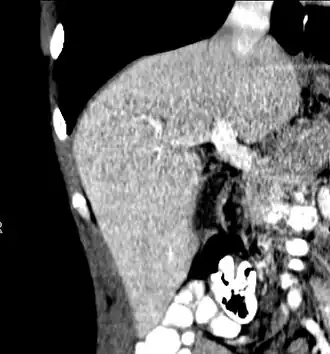

Left lobe liver tumor

After resection of left lobe liver tumor